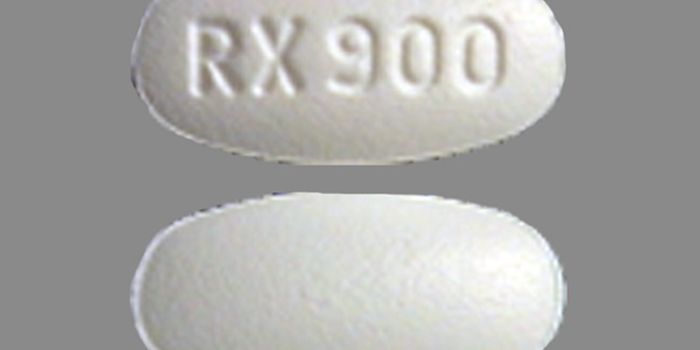

APR 27, 2016ImmunologyOriginally developed as an anesthetic in 1926, phencyclidine (PCP), also known as “angel dust,” was disconti ...